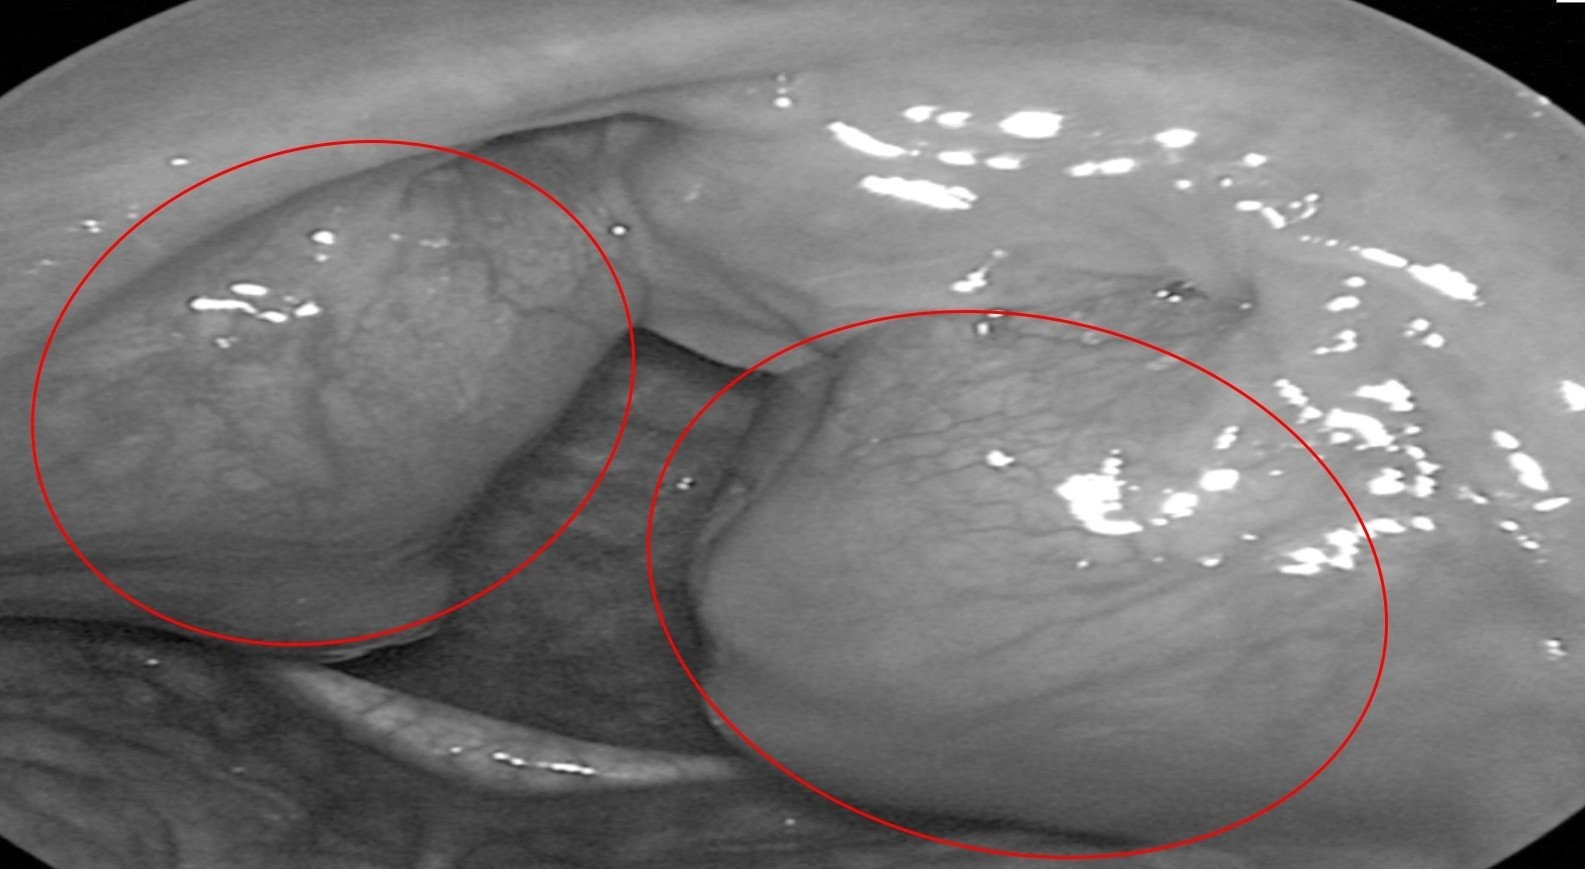

Khối amidan kích thước lớn che lấp gần hết đường thở của bệnh nhân.

Qua thăm khám tại Bệnh viện Đa khoa Tâm Anh TP.HCM, ThS.BS.CKI Nguyễn Thị Hương - khoa Tai Mũi Họng - phát hiện anh Bảo bị viêm amidan quá phát độ 4 (mức độ nặng nhất), gây ngưng thở khi ngủ, cần phẫu thuật cắt bỏ.